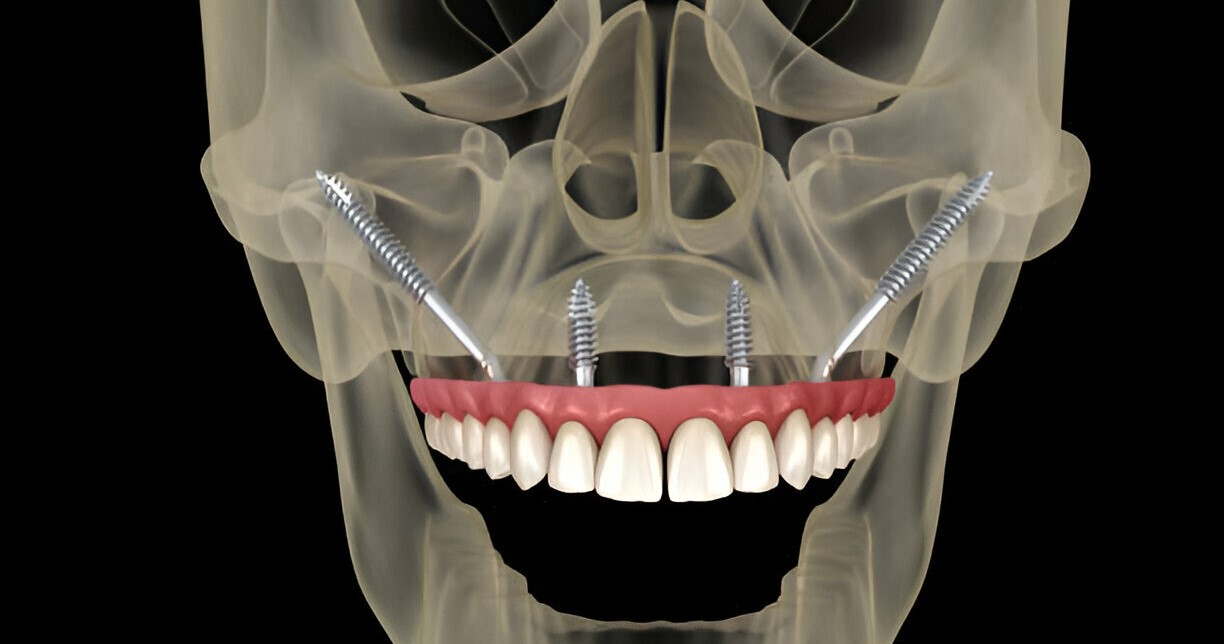

Zygomatic Implants

Zygomatic dental implants are an innovative solution for tooth replacement, specifically designed for individuals with significant bone loss in the upper jaw’s cheekbone area